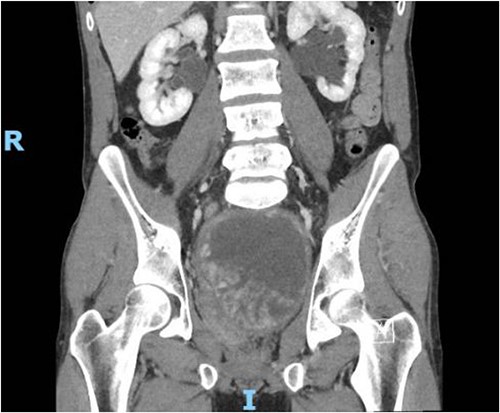

The patient presented to the ED 3 months later with urinary retention and pain; this was relieved with catheterization. A CT scan revealed that his tumor had slightly increased in size (Fig. 1). He had an AUA symptom index of 35. Due to the refractory nature of his obstructive symptoms, he was scheduled for a TURP 2 weeks later, which again revealed leiomyoma. He was kept on interval follow-up for the next 2 years. During that time his PSA was 1.13 ng/ml. Magnetic resonance imaging (MRI) pelvis 2 years later showed the mass appeared to communicate with the posterior bladder neck (Fig. 2). His baseline renal function kept worsening (Creatinine 1.4 mg/dl); at that time, the patient was counseled regarding his treatment options, and he opted for surgery which he was told may require the removal of the prostate with loss of ejaculatory and/or erectile function.

MRI Pelvis (contrast) June 2021: well-marginated complex solid, cystic, and septated pelvic mass with multiple sites of enhancement and restricted diffusion; the mass appears to communicate with the bladder neck.